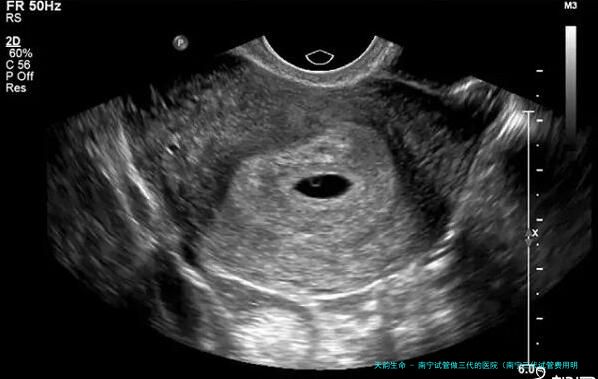

3、多囊样改变

如同在B超监测下发现患者一面或两侧卵巢内有12个之上的小卵泡,卵泡很难成熟,一般来说可确诊为多囊卵巢综合症。